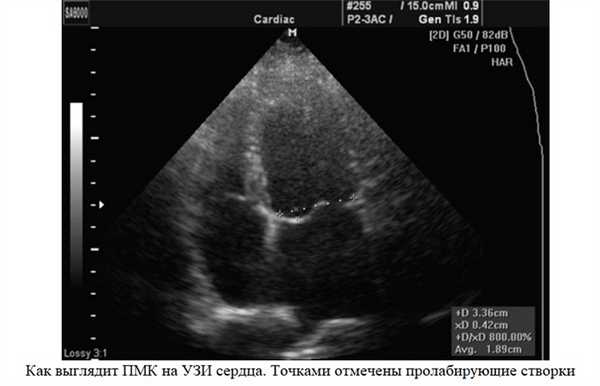

- Эхокардиография (УЗИ сердца). Здесь врач может обнаружить такие признаки болезни, как провисание створок митрального клапана (задней или сразу обеих) в полость левого предсердия в середине систолы, в позднюю систолу или во всю систолу. Эхокардиография - это одно из самых важных обследований в диагностике ПМК у пациента.

Эхокардиография (УЗИ сердца) - это главный метод исследования для диагностики ПМК. С его помощью оценивается тяжесть пролапса: степень пролабирования створок и регургитации. Под пролабированием подразумевается то, насколько створки клапана прогибаются в полость левого предсердия.

- смещение створок в момент систолы желудочков, пролабирование (прогибание) створок больше 3 мм.